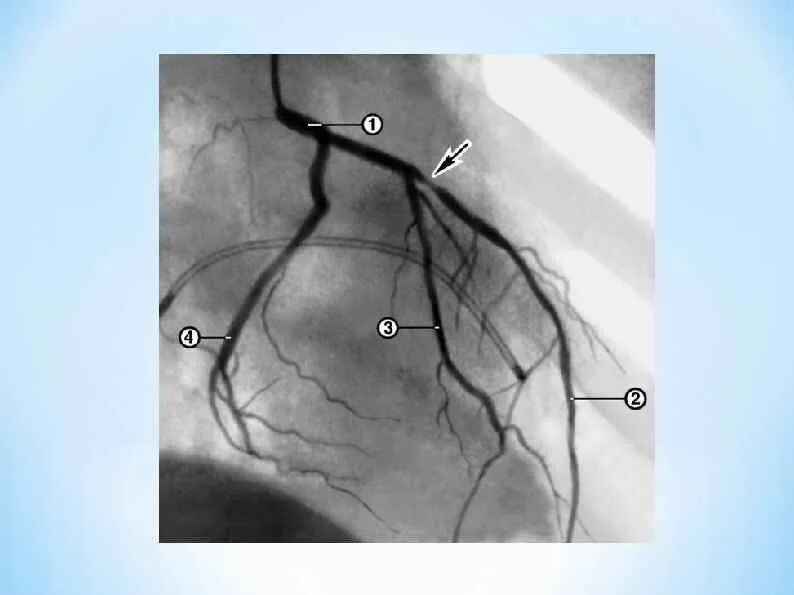

Атеросклероз левой коронарной артерии